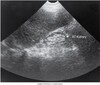

What pathology is seen here?

Phleboliths